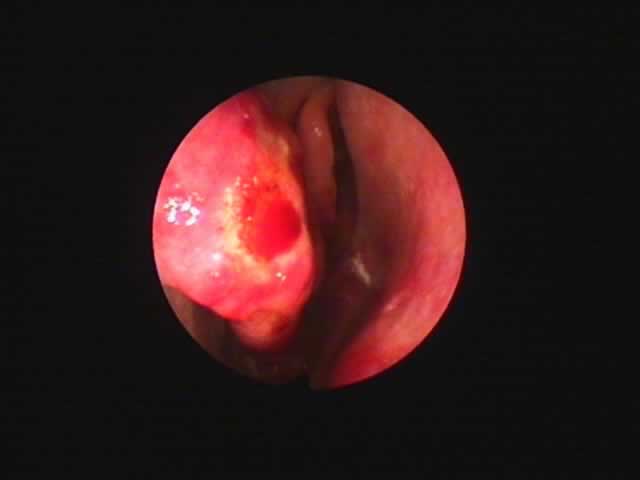

| 左扁桃術直後(31歳男性,6月9日) 数カ所針電極を刺入 | 白い部分が変性部位(6月11日) | 右扁桃術直後(7月7日) |